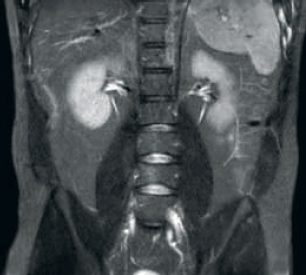

Resultado: resolución de imagen y SNR mejoradas

Mayor consistencia y mejor calidad de imagen La tecnología de recepción de RF dStream digitaliza la señal del resonador magnético directamente en la bobina de radiofrecuencia, lo que resulta en un aumento de hasta un 40 % más de la SNR* en todo el volumen de la imagen. Flujo de trabajo simplificado y rendimiento mejorado La bobina posterior integrada en la mesa elimina el manejo de la bobina en el 60 % de los exámenes. Las ligeras bobinas anteriores conformadas y las conexiones de bobina de un solo cable y de una sola mano contribuyen a la facilidad operativa.